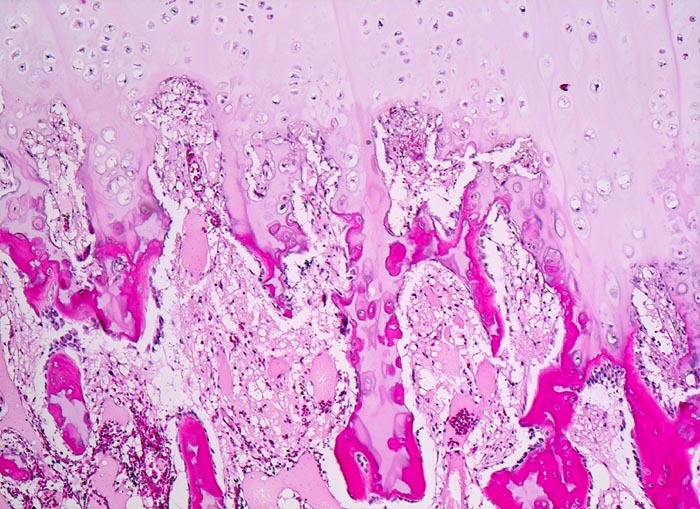

Osteochondrome sind breitbasig dem Knochen aufsitzende oder gestielte knöcherne Tumoren, die von einer 1-6mm dicken Kappe aus hyalinem Knorpel bedeckt werden. Zwischen Knorpel und Knochen liegt eine Zone enchondraler Ossifikation, die der normalen Wachstumsfuge ähnelt und den Ausgangspunkt für die Grössenzunahme des Tumors bei noch nicht abgeschlossenem Skelettwachstum darstellt. Der hyaline Knorpel wirkt etwas unorganisiert und ist bedeckt von einer dünnen Schicht Perichondrium.

• Kappenförmiges hyalines Knorpelgewebe ohne Zellatypien sitzt auf einem knöchernen Stiel. Die Knorpelkappe ist 2mm dick.

• Übergang des Knorpels in enchondrale Ossifikationszone wie in einer Epiphysenfuge: Knochen wird abgelagert entlang von linearen Knorpelsäulen.